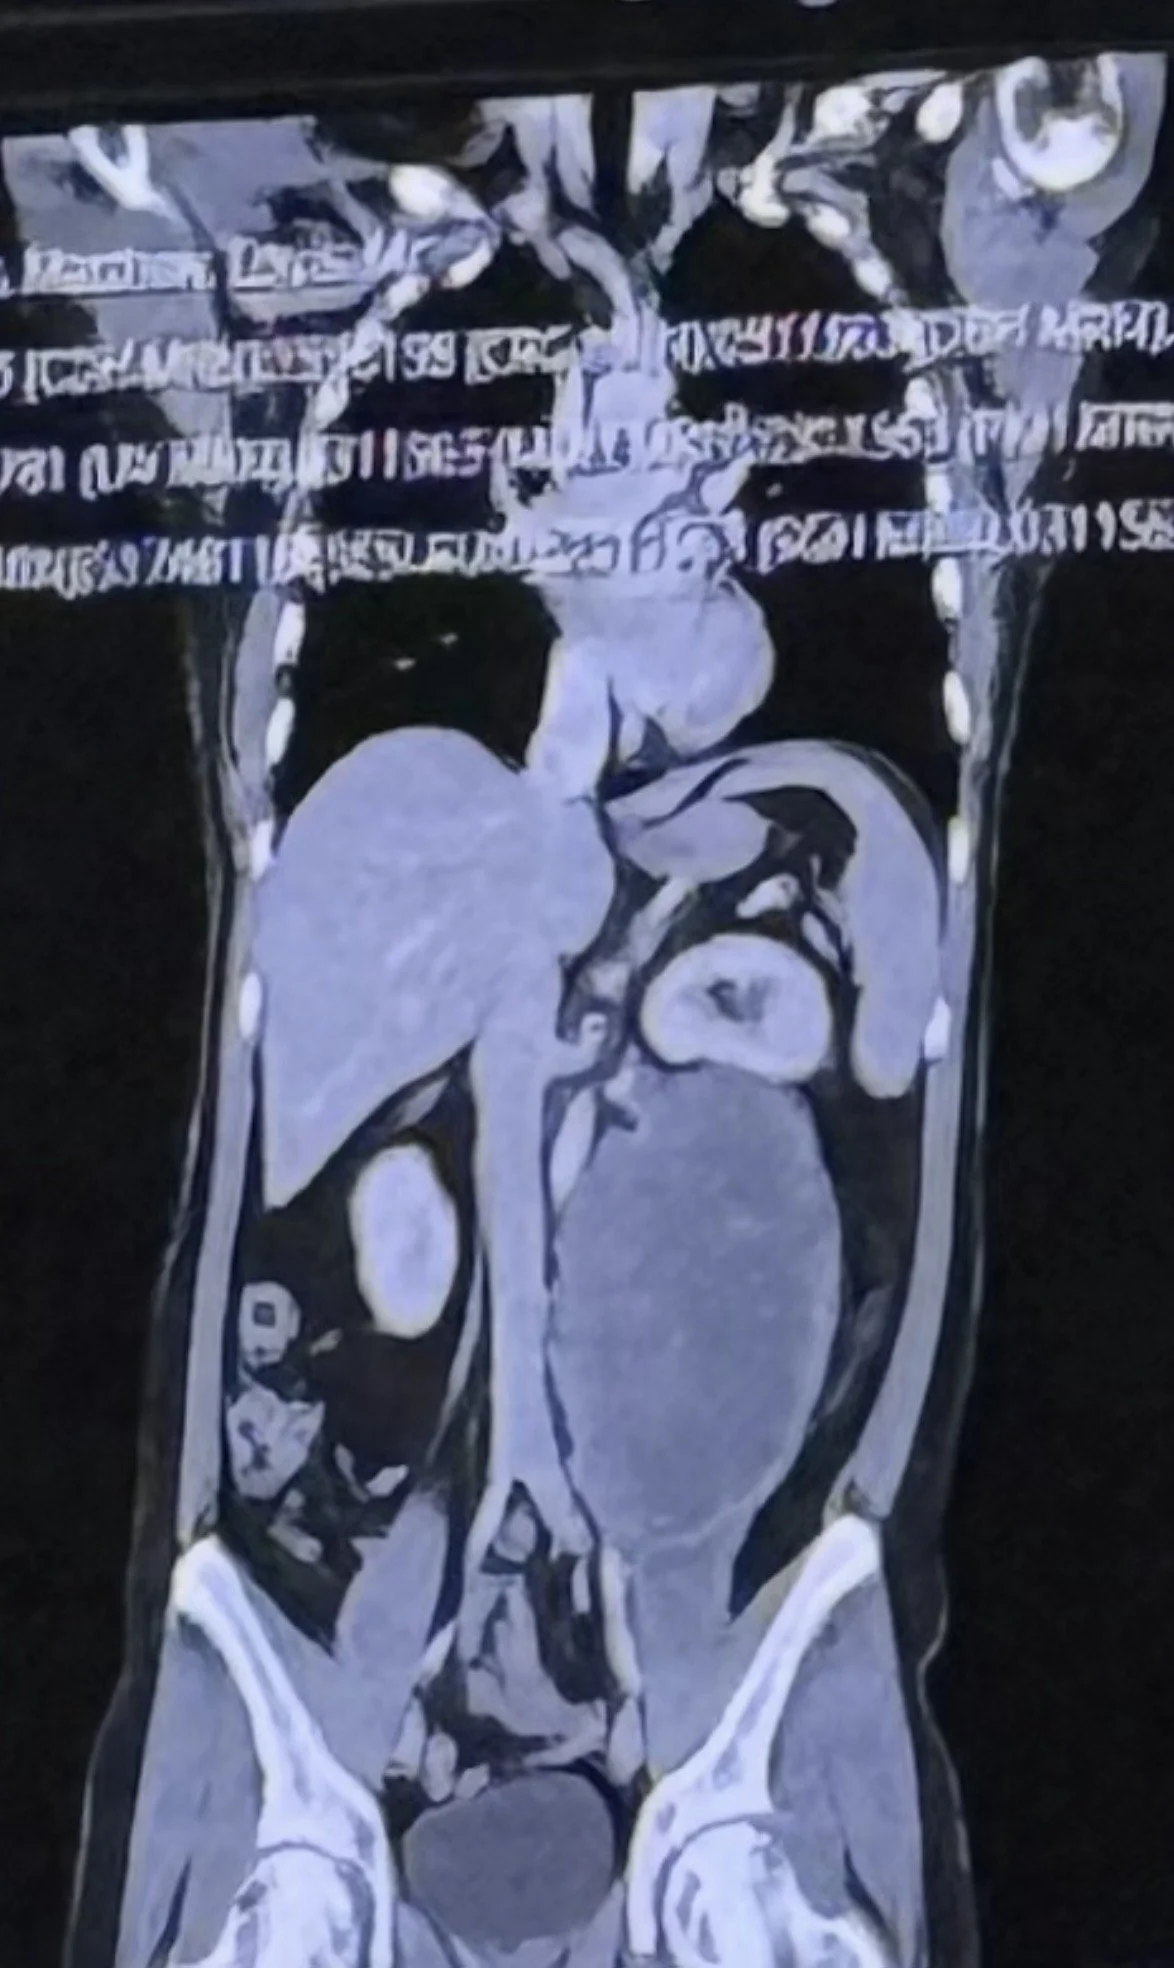

In this powerful episode of It Takes Balls, Australian guest Matt P shares his extraordinary path to a testicular cancer diagnosis that initially appeared to be a rare and life-threatening sarcoma. What began as persistent back pain, rising blood pressure, and unexplained fatigue spiraled into the discovery of a football-sized tumor wrapped around major organs, including his kidney and psoas muscle. Matt opens up about the terrifying weeks when doctors believed he faced a 40–50% survival rate, until a biopsy revealed something astonishing: the massive abdominal tumor was actually metastatic embryonal carcinoma, a highly aggressive but highly chemo-responsive form of testicular cancer.